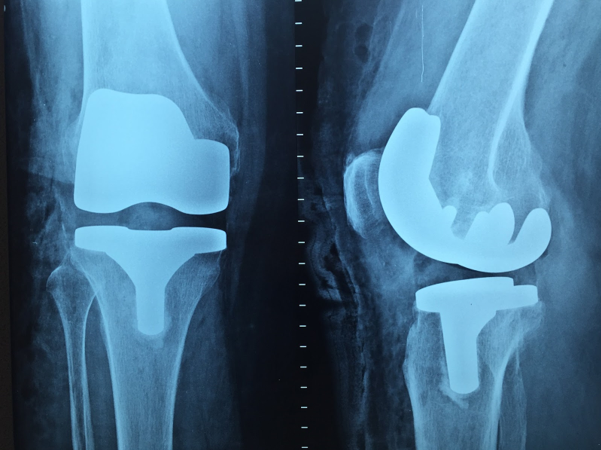

Knee Replacement

Knee replacement is also known as knee arthroplasty, is a surgical procedure to replace the knee damaged by arthritis or injury. It is the artificial knee replacement form the knee joint, along with the kneecap. This surgery may be considered for someone who has facing arthritis or knee problems.

The goal of knee replacement surgery is to replace the parts of the knee joint that have been damaged due to arthritis and injury. Knee replacement relief knee pain that cannot be controlled by other treatments. We are the best orthopaedic hospital in Patna who will provide you with professional competence and warm patient care.